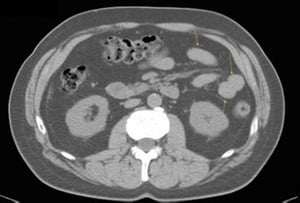

CT-Scan von Abdomen und Becken mit normaler Anatomie ohne Kontrastmittel (Folie 17)

Dieses Bild zeigt das Kolon (Pfeile).

© Springer Science+Business Media